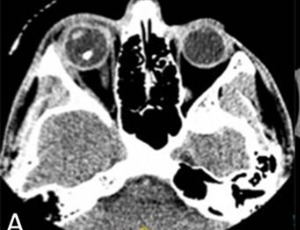

An atypical case of compressive optic neuropathy and cranial nerve 6th palsy caused by a cholesterol granuloma

In this case report we present an unusual case of orbital cholesterol granuloma associated with compressive optic neuropathy and cranial nerve 6th palsy. Cholesterol granuloma results from a foreign body response to the presence of crystallized cholesterol. Cholesterol granuloma affecting the orbit are a rare presentation as they typically occur in the petrous apex of the temporal bone.